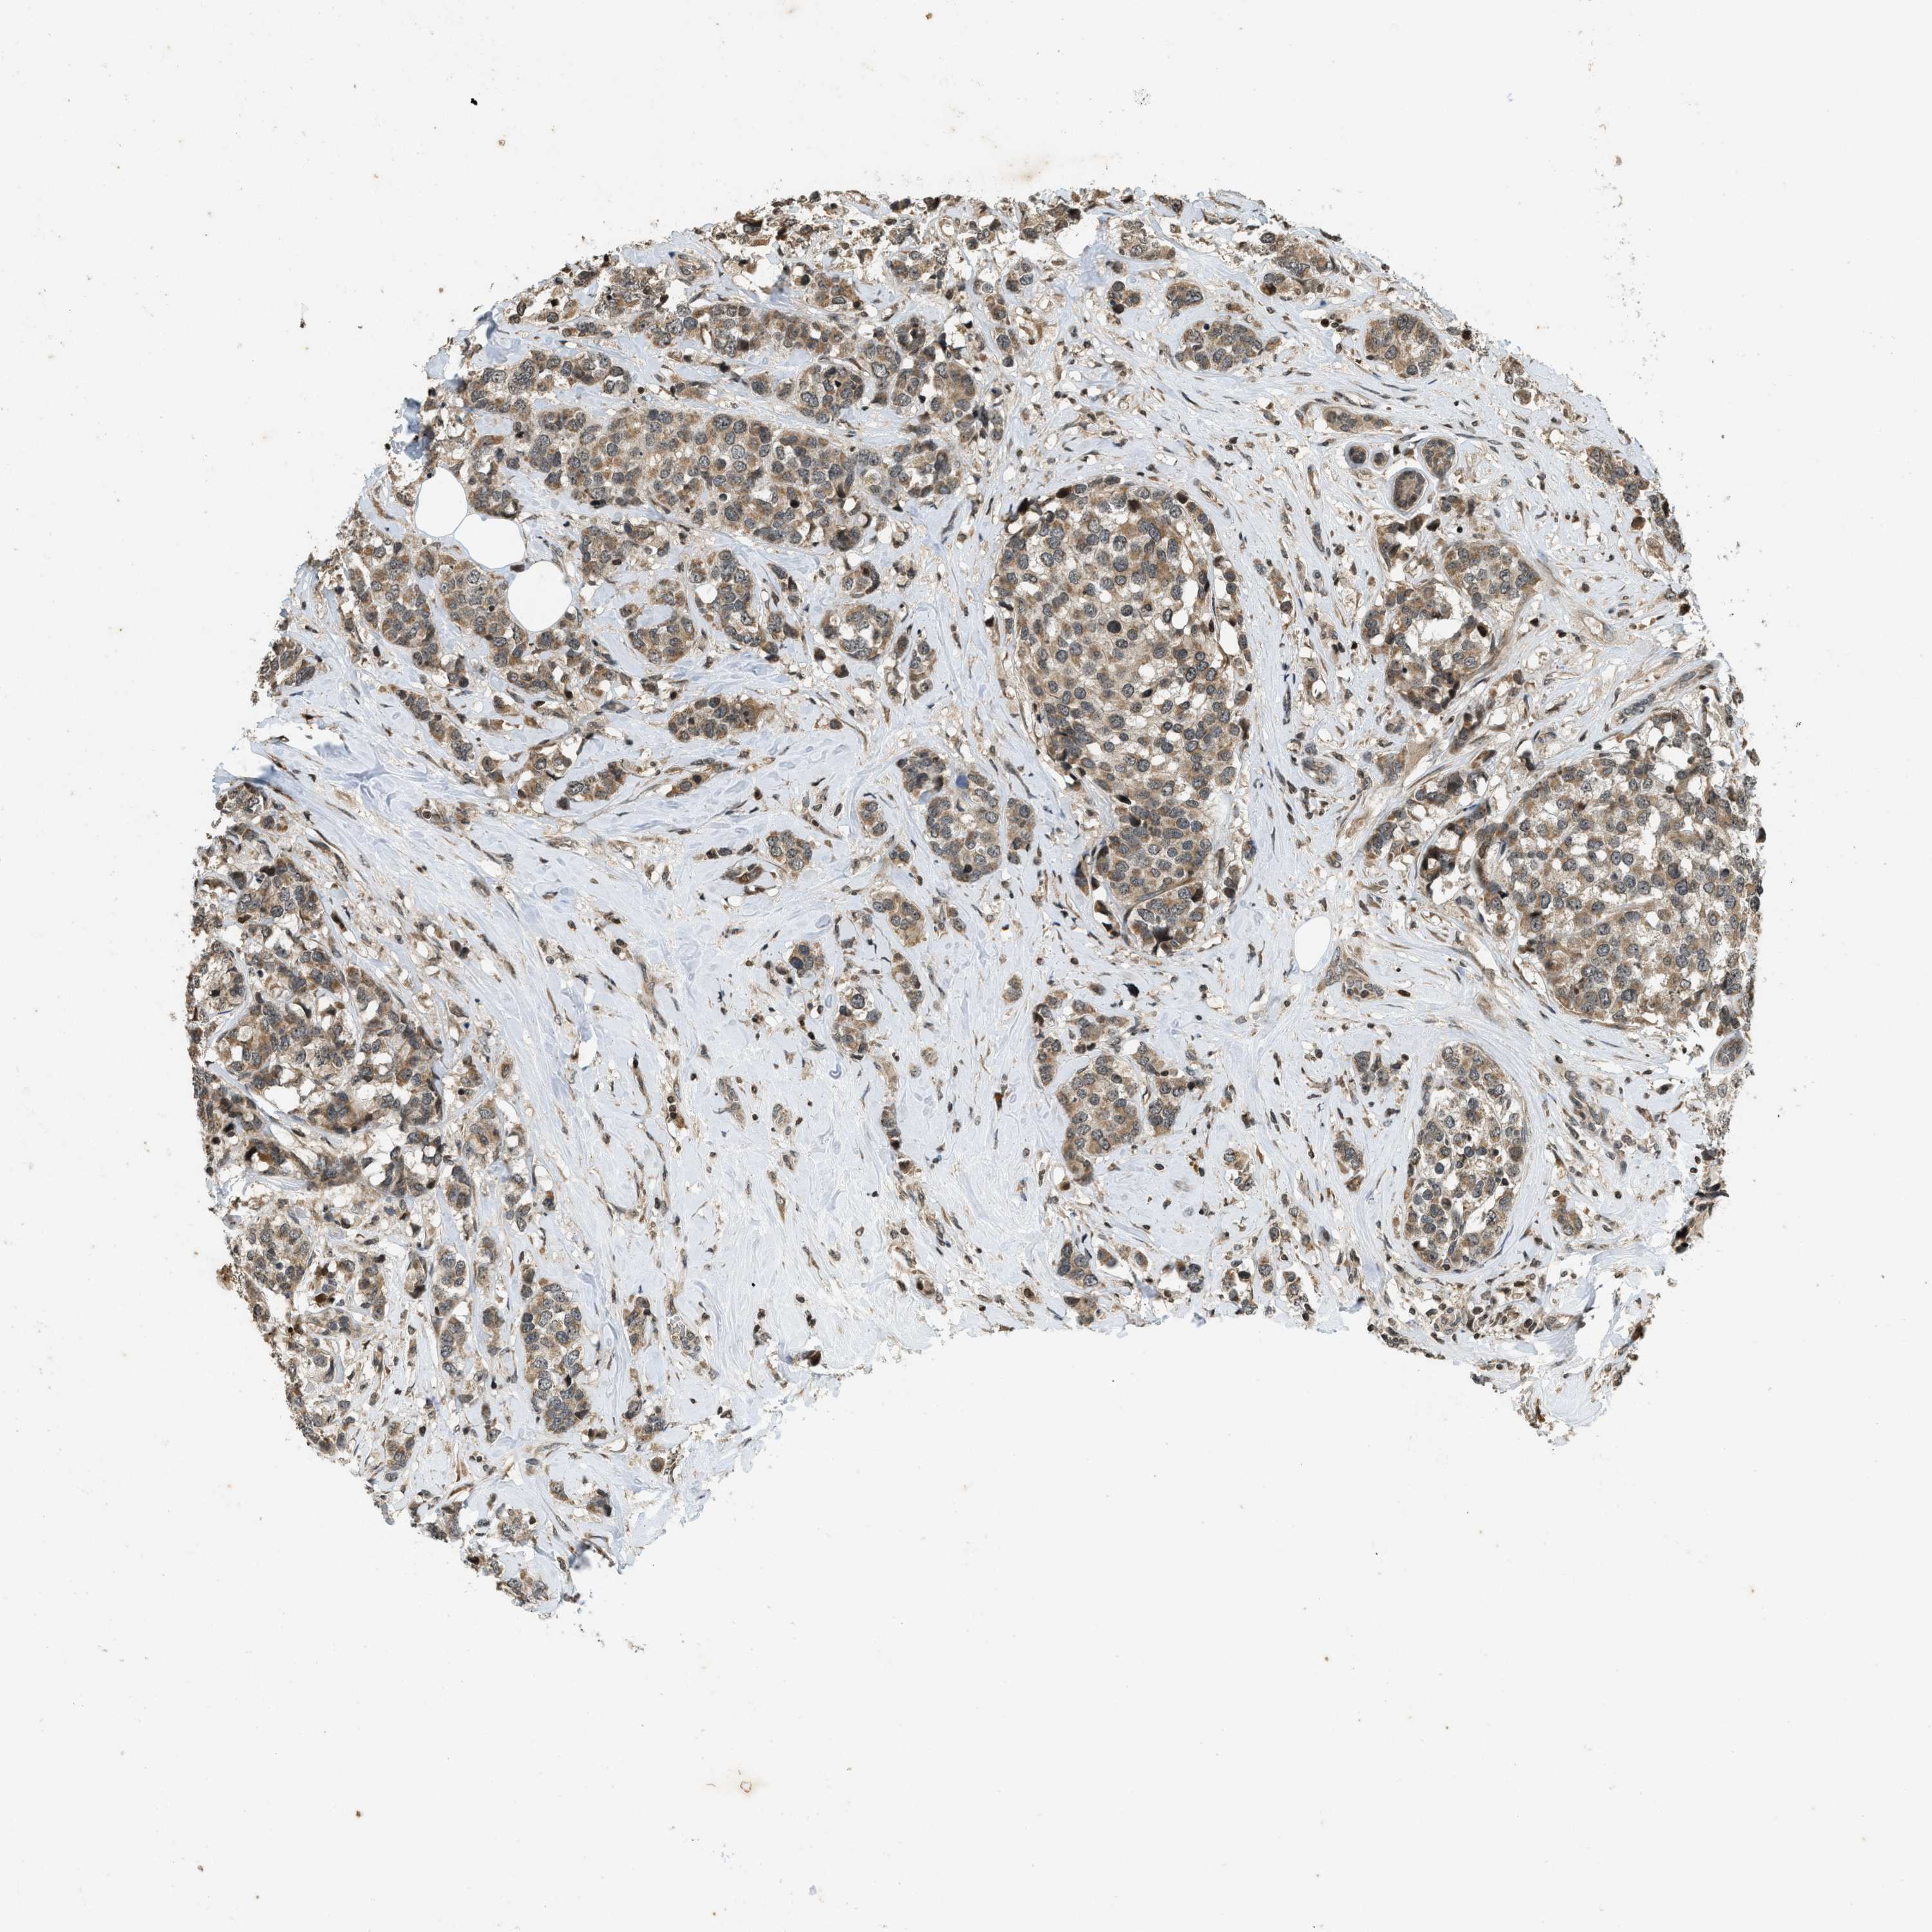

CANCER BREAST CANCER Show tissue menu

BRCA TCGA BRCA VALIDATION PROTEIN EXPRESSION